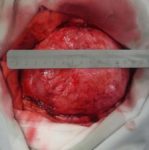

během operace